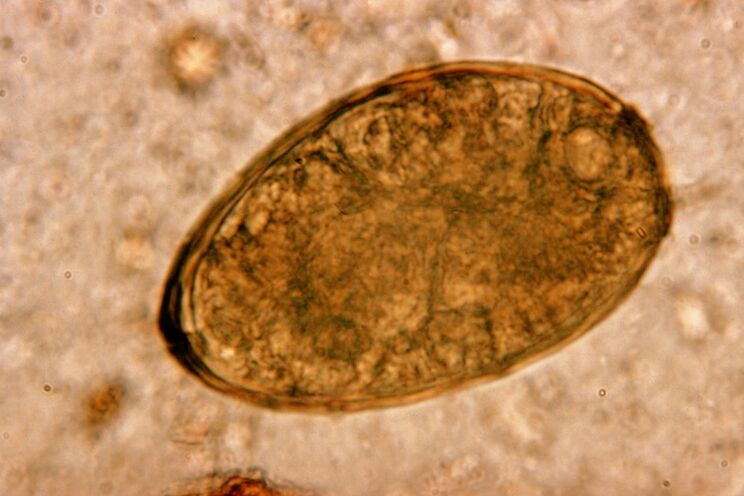

Viermi rotunzi, viermi rotunzi, trăiesc și se reproduc în intestine. Infecția cu acestea se produce prin ouăle care intră în organism cu alimente sau din mâini și obiecte folosite de o persoană infectată. Sol, fructe, legume, carne și pește prost gătite - toate acestea pot introduce ouă de helminți în corpul uman.

Merită de știut! Viermii rotunzi provoacă o tuse uscată. Migrând prin sistemul circulator, larvele lor pătrund în organele respiratorii - bronhii, trahee, plămâni - iritând receptorii și provocând acest simptom. Perioada de migrare a larvelor în tot corpul este de una până la două săptămâni.

Viermii rotunzi sunt foarte răspândiți, așa că tusea pe fondul ascariazei este un fenomen tipic. Infecția cu viermi rotunzi apare pe căi tradiționale pentru helmintiază. Acestea includ contactul cu solul, consumul de fructe și legume nespălate și mâinile murdare.

Larvele de Ascaris provoacă problema afectând mecanic țesuturile sistemului respirator. Acest lucru se întâmplă în timpul fazei de migrare a parazitului. Mecanismul și secvența impactului viermilor rotunzi asupra sistemului respirator uman este după cum urmează.

Odată ajunse în tractul gastrointestinal, ouăle de viermi rotunzi, sub influența propriilor enzime și a sucului digestiv, își vărsă coaja, transformându-se în larve. Acestea din urmă sunt înzestrate cu capacitatea de a pătrunde prin peretele intestinal în fluxul sanguin. După care sunt transportate de sânge în tot corpul - ajungând la ficat, inimă, plămâni și tractul respirator.

Pe membrana mucoasă a traheei se află cili, care transportă larva în sus cu mișcările lor reflexe. În acest caz, receptorii sunt iritați și apare o tuse, aruncând helminți în gură, de unde fie sunt scuipați, fie înghiți, revenind în intestine.

Pentru informația dumneavoastră! Tusea cu ascariaza este de obicei un fenomen pe termen scurt. Dar dacă infestarea este de natură recurentă, poate deveni aproape permanentă.